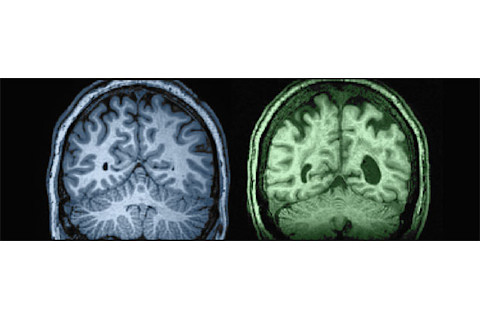

扫描图的故事:衰退中的大脑

大脑会随着年龄的增长而萎缩,导致各种各样的缺陷。俄勒冈健康与科学大学的神经科学家杰弗里·凯利用核磁共振扫描(如下图所示)来追踪这一过程。他说,萎缩发生在血流量减慢时,减少了大脑细胞可用的氧气和营养物质。这导致滋养和修复神经元的能力下降,并伴随认知能力下降。——艾玛·布莱斯

蛛网膜下腔 左图:27岁大脑 头骨与大脑之间的空间在年轻时紧密。 右图:87岁大脑 神经元网络萎缩,空间变宽,心理处理速度减慢。

脑室 左图:27岁 充满脑脊液的脑室缓冲大脑;年轻时它们狭窄。 右图:87岁 脑室随灰质萎缩而扩大;执行功能下降。

白质束 左图:27岁 由神经纤维和神经胶质细胞组成的神经通路高效传输信号。 右图:87岁 神经胶质细胞随年龄萎缩,扰乱信号传输并导致认知能力下降。所有图片均由俄勒冈大脑衰老研究中心、波特兰退伍军人医疗中心和俄勒冈健康与科学大学提供。 一些大脑如何保持敏锐